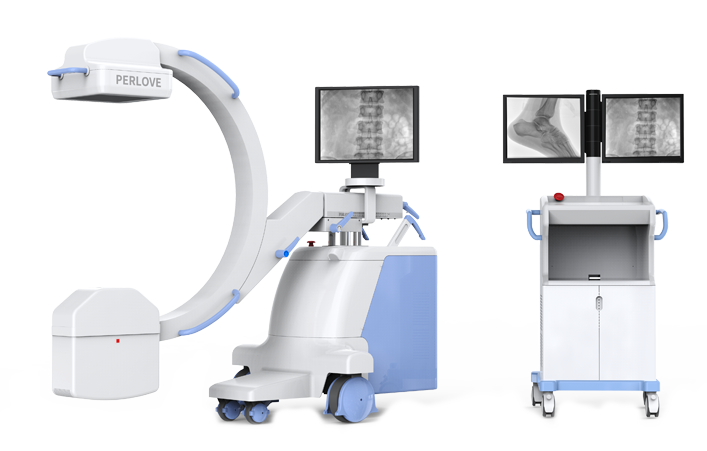

PLX118F系列

移动式平板C形臂X射线机

动态板C形臂 开启清晰影像新篇章 PLX118F

临床适用科室:骨科、普通外科、矫形外科、创伤外科、泌尿外科、脊柱外科、疼痛外科、消化科、妇科等科室。

大尺寸动态平板探测器,高DQE、低噪声、图像清晰。采用多分辨率图像增强处理技术,不同部位不同图像处理算法,满足客户多样化的需求。

采用智能变频脉冲透视技术,优化图像质量的同时降低辐射剂量,呵护医患健康

图形化操控界面设计:设有多种人体特征摄影参数,操作简便。双向红光十字定位系统:实现无射线下的高效定位。信息共享:遵循DICOM3.0格式接口,可无缝对接云PACS系统。

多角度自由旋转,满足患者复杂摆位需求。